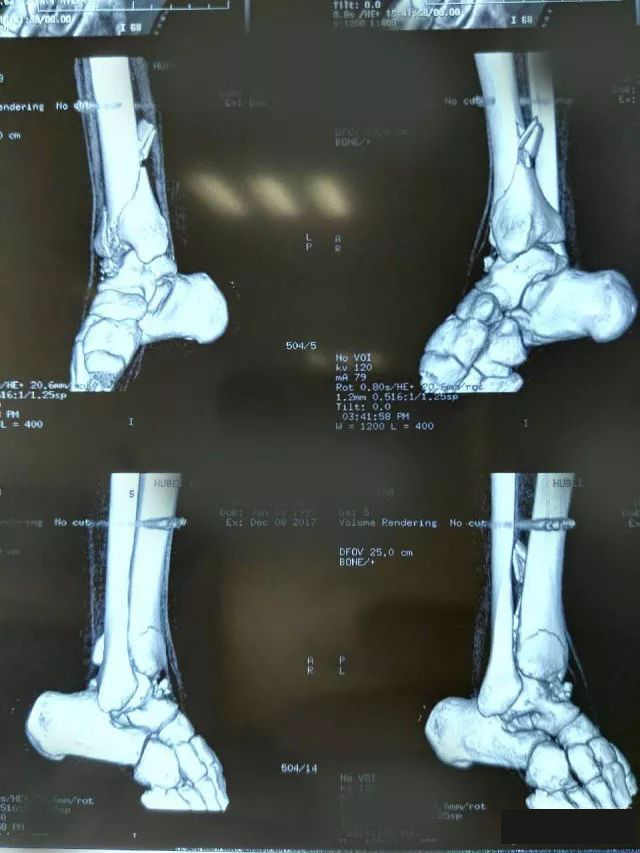

一起来看一个病例:男,20岁,摔倒右踝3天,体格检查示右小腿下段肿胀压痛,活动受限,运动感觉可,诊断为右侧 Pilon骨折。X片及CT三维图如下,欢迎投票并在评论区附上理由。